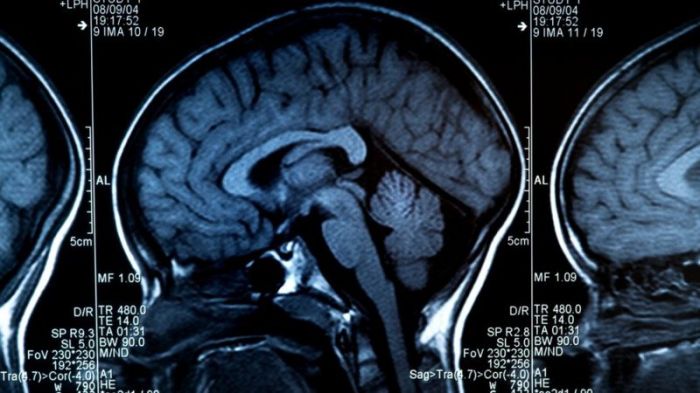

قالت هيئة بريطانية معنية بمراقبة البيانات إن الشركات في المستقبل قد تستخدم تقنية مراقبة المخ لتتبع الموظفين أو تعيينهم. وأضاف مكتب مفوض المعلومات البريطاني أنه يوجد خطر حقيقي من حدوث تمييز في حالة عدم تطوير “التكنولوجيا العصبية” واستخدامها بشكل صحيح.

ويعد تقرير “مستقبل التكنولوجيا: التكنولوجيا العصبية” أول تقرير من الهيئة عن “البيانات العصبية”، وهي بيانات مستمدة من المخ والجهاز العصبي.

وتقول الهيئة إن التكنولوجيا العصبية مستخدمة بالفعل في قطاع الرعاية الصحية، مع تطبيق لوائح صارمة.